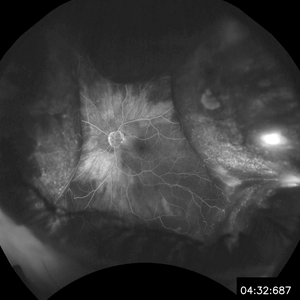

Choroidal Detachment

Jan 6 2020 by Sarah Oelrich

Photographer: Sarah Oelrich CRA COT OCT-C

Imaging device: Optos

Condition/keywords: choroidal detachment, detachment, FA late phase